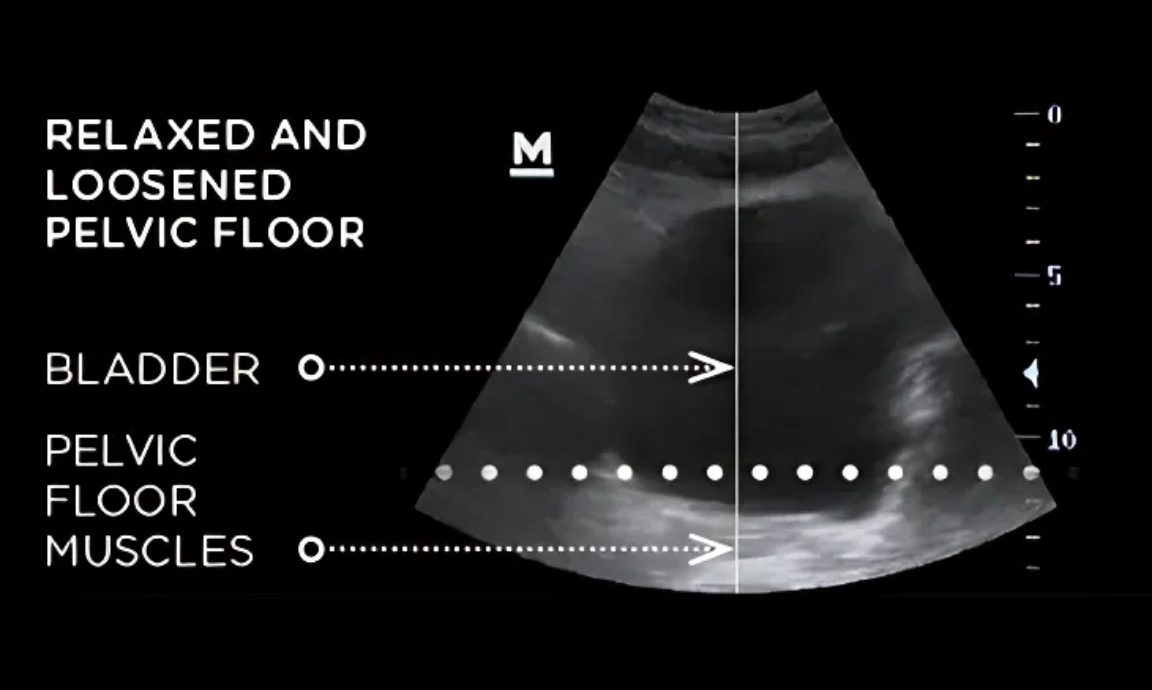

Emsella works its magic by delivering high-intensity focused electromagnetic energy to your pelvic floor, inducing thousands of muscle contractions during each session. This innovative stimulation re-educates and strengthens your pelvic muscles, enhancing neuromuscular control and significantly improving bladder function. It’s like a workout for your pelvic floor—no sweat required!

Urinary incontinence is the involuntary leakage of urine, which can occur due to various factors such as weak pelvic floor muscles, aging, hormonal changes, or childbirth. It can significantly impact quality of life, but treatments like Emsella can help restore control.

Emsella works by delivering electromagnetic energy to the pelvic floor, inducing thousands of muscle contractions during each session. This re-educates and strengthens the pelvic muscles, enhancing neuromuscular control and improving bladder function.